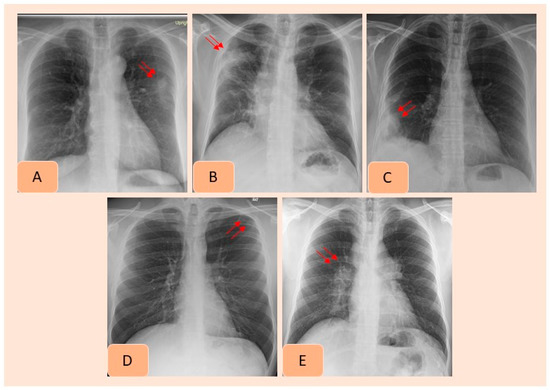

Figure 2. AI-detected CXR findings that were not documented in the radiology reports included pulmonary nodule (A), consolidation (B), pleural effusion (C), pneumothorax (D) and hilar prominence (E).

Table 3 summarizes country-wise distribution of CXR findings at the vendor-recommended thresholds. There were variations in the performance of the algorithm across the Indian and US sites, although the differences were not statistically significant (p > 0.2). Pneumothorax and mediastinal widening had the lowest AUCs for the AI algorithm, whereas highest AUCs were reported for pleural effusions, enlarged cardiac silhouette, hilar prominence and rib fractures. Figure 2 presents examples of the AI-detected CXR findings which were not reported in the radiology reports. Figure 4 presents findings missed by both the AI algorithm and in the original radiology reports.